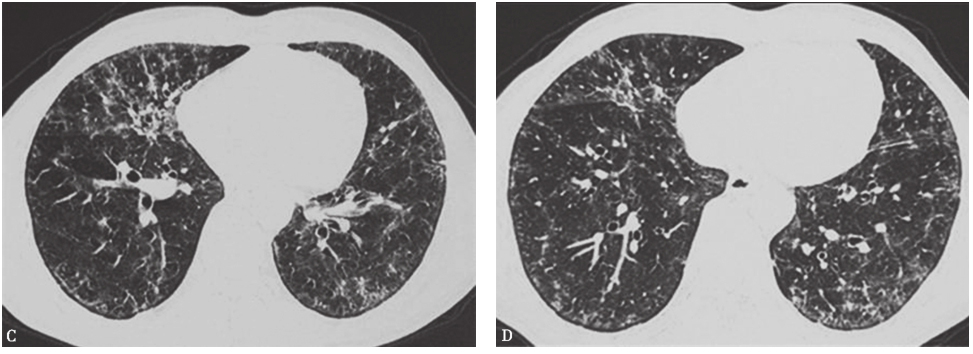

巨细胞间质性肺炎(giant cell interstitial pneumonia,GIP):是暴露于含有钴、碳化钨等硬金属及其化合物引起的少见职业相关性间质性肺疾病。其典型胸部CT表现为弥漫性磨玻璃影、小结节影、广泛网状影和牵拉性支气管扩张改变,以及大小不等的实变影(图12)。晚期患者可见肺部广泛的结构扭曲和蜂窝样改变。GIP最终诊断应该根据职业接触史、影像学特征和病理学等证据。本例患者从事钻孔工作8年,接触金属粉尘较多,有职业接触史,影像学特征也较符合GIP,但仍需获得病理学检查结果以明确诊断。

图12巨细胞间质性肺炎胸部影像学表现

男性患者,32岁,从事刀具磨制工作9年,经支气管肺活检病理证实为巨细胞间质性肺炎。CT示两肺散在磨玻璃影、小结节影、小片实变影、牵拉性支气管扩张